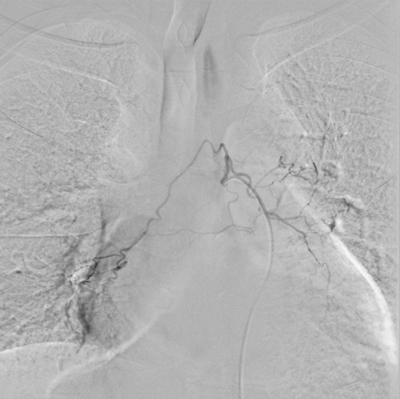

患者王某、男、55岁,因“反复间断咯血3月余”入住我院,曾因间断咯血,多次行止血药物等治疗,但症状仍有反复。此次咯血量大,病情危重,药物治疗效果差,经院内多学科讨论,在湖北民族大学附属民大医院副主任医师万金城、主治医师姚蓬指导下,制定血管介入治疗方案,并顺利完成了支气管动脉造影术+支气管动脉栓塞术,术后患者咯血症状明显好转。

术前 术后